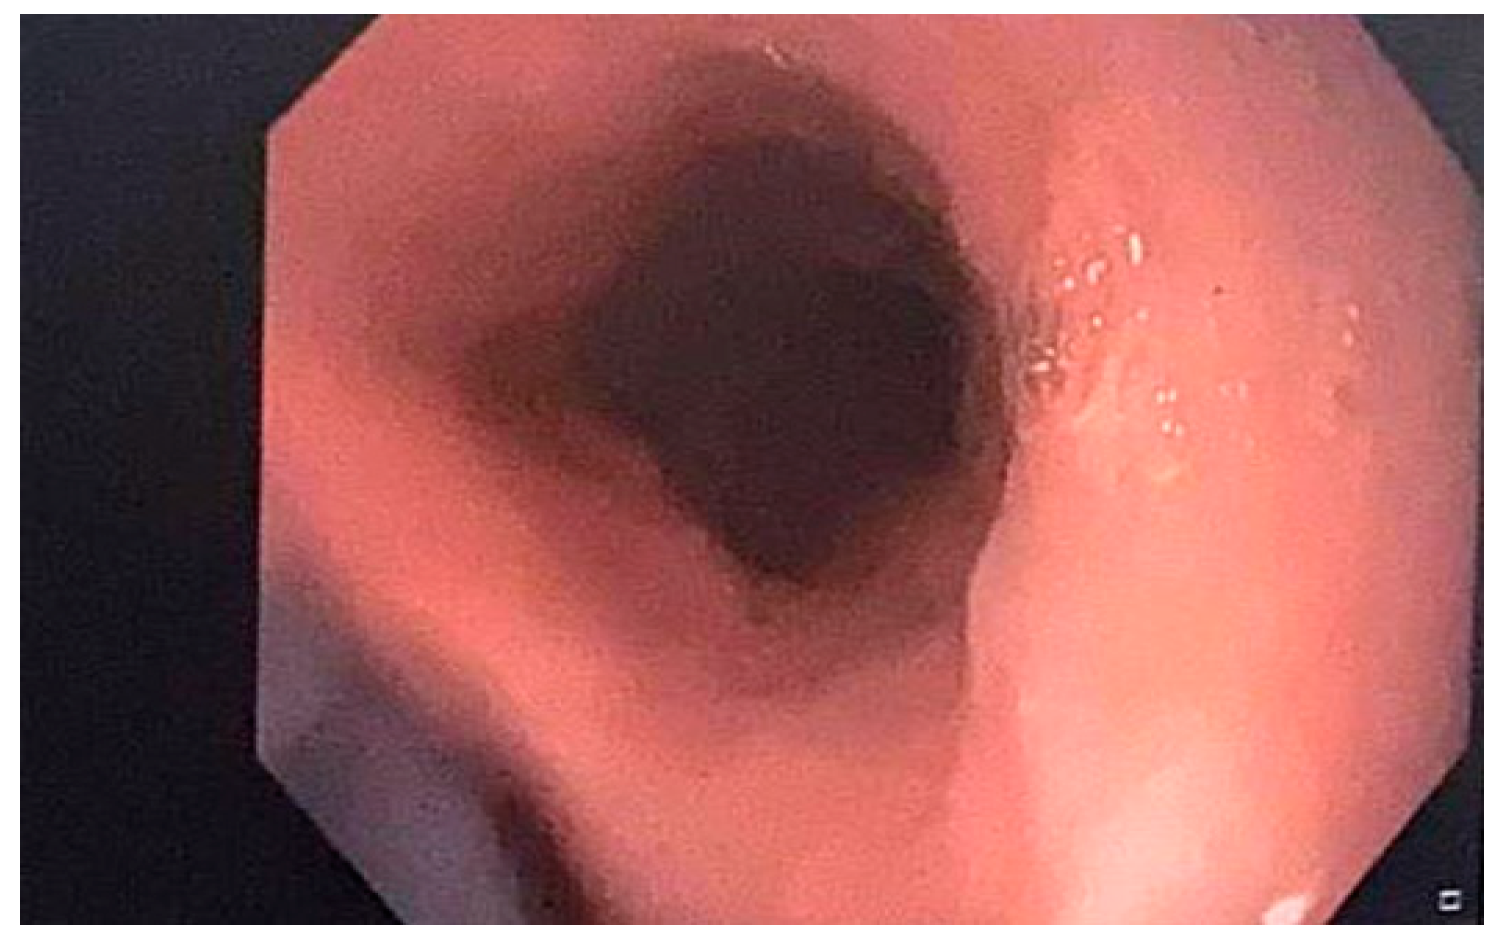

Discussing the case with the patient’s cardiologist, apixaban was discontinued and a treatment with low-molecular-weight heparin twice daily was initiated during her hospital stay. After discharge, a treatment with rivaroxaban was prescribed. She also underwent acid suppression with 40 mg of a PPI (pantoprazole) twice daily and a treatment with an oral iron supplement for six months. A liquid diet was initiated for 24 h. Additionally, she was advised to ingest these medicines with enough water and stay seated for at least 30 min after taking any drugs to prevent them from adhering to the esophageal mucosa. A follow-up upper GI endoscopy at one month revealed a significantly improved esophageal appearance (Figure 2).

Figure 2.

Improved endoscopic appearance of the esophageal mucosa one month after treatment.